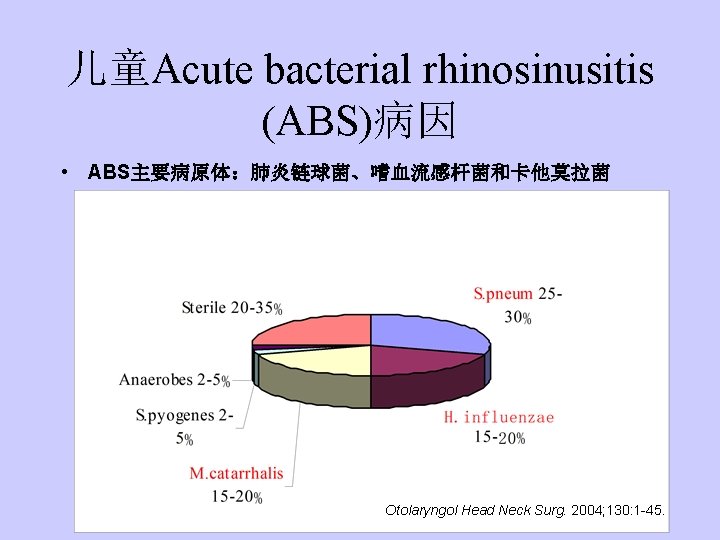

儿童Acute bacterial rhinosinusitis (ABS)病因 • ABS主要病原体:肺炎链球菌、嗜血流感杆菌和卡他莫拉菌 Otolaryngol Head Neck Surg. 2004; 130: 1 -45.